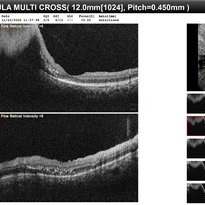

RPE rip in a case of Idiopathic polypoidal choroidopathy RPE rip in a case of Idiopathic polypoidal choroidopathyOct 23 2022 by Anjana Mirajkar, MS Ophthalmology OCT image in a of 61 year old male with RPE rip in a case of Idiopathic Polypoidal Choroidopathy. Photographer: Dr. Anjana Mirajkar -Retina Foundation, Ahmedabad Condition/keywords: Idiopathic polypoidal choroidopathy, RPE rip